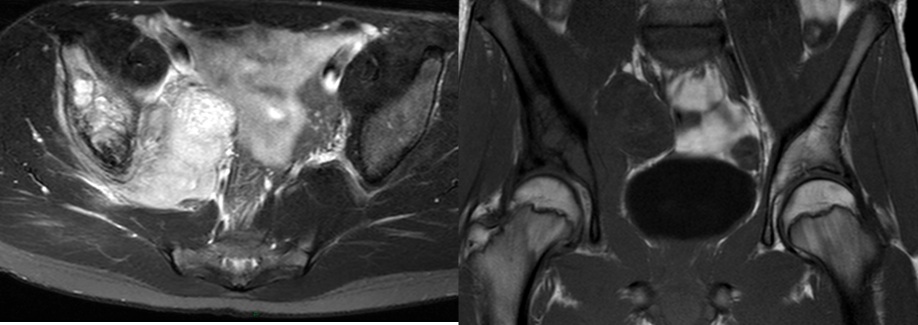

Figure 5 for case Ewing Sarcoma

Figure 5

Discussion

Diagnosis

Ewing Sarcoma